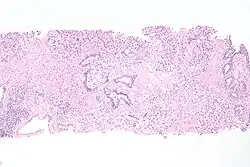

| Histopathology of transitional carcinoma of the urinary bladder. Transurethral biopsy. Hematoxylin and eosin stain. | |

Histopathology of urothelial carcinoma of the urinary bladder, showing a nested pattern of invasion. Transurethral biopsy. H&E stain -

Histopathology of urothelial carcinoma of the urinary bladder. -